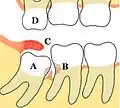

Некоторые проблемы, которые могут возникнуть или не возникнуть с третьими молярами: A Мезиоретинированный, частично прорезавшийся третий моляр нижней челюсти; B Кариес зубов и дефекты пародонтита, связанные как с третьими, так и со вторыми молярами, вызвано упаковкой пищевых продуктов и плохим доступом к методам гигиены полости рта; C Воспалённый капюшон, покрывающий частично прорезавшийся третий нижний моляр, со скоплением остатков пищи и бактерий под ним; D Верхний третий моляр перерос, разрывается из-за отсутствия контакта с противоположным зубом и может начать травматически окклюзию в крышечку над нижним третьим моляром. Зубы без сопротивления обычно острые, потому что они не притуплены другим зубом.